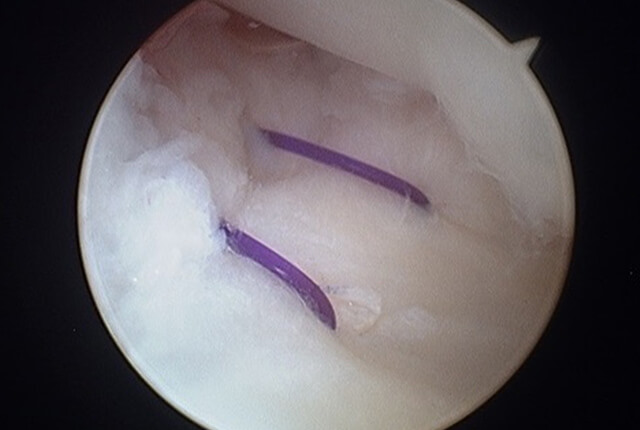

まずは手関節鏡視下にTFCCを観察します。

TFCC損傷の状況、尺骨variance、DRUJ不安定性などから手術方法を決定します。

TFCC縫合術

DRUJ不安定性高度のTFCC損傷は尺骨遠位に縫合する手術法があります。